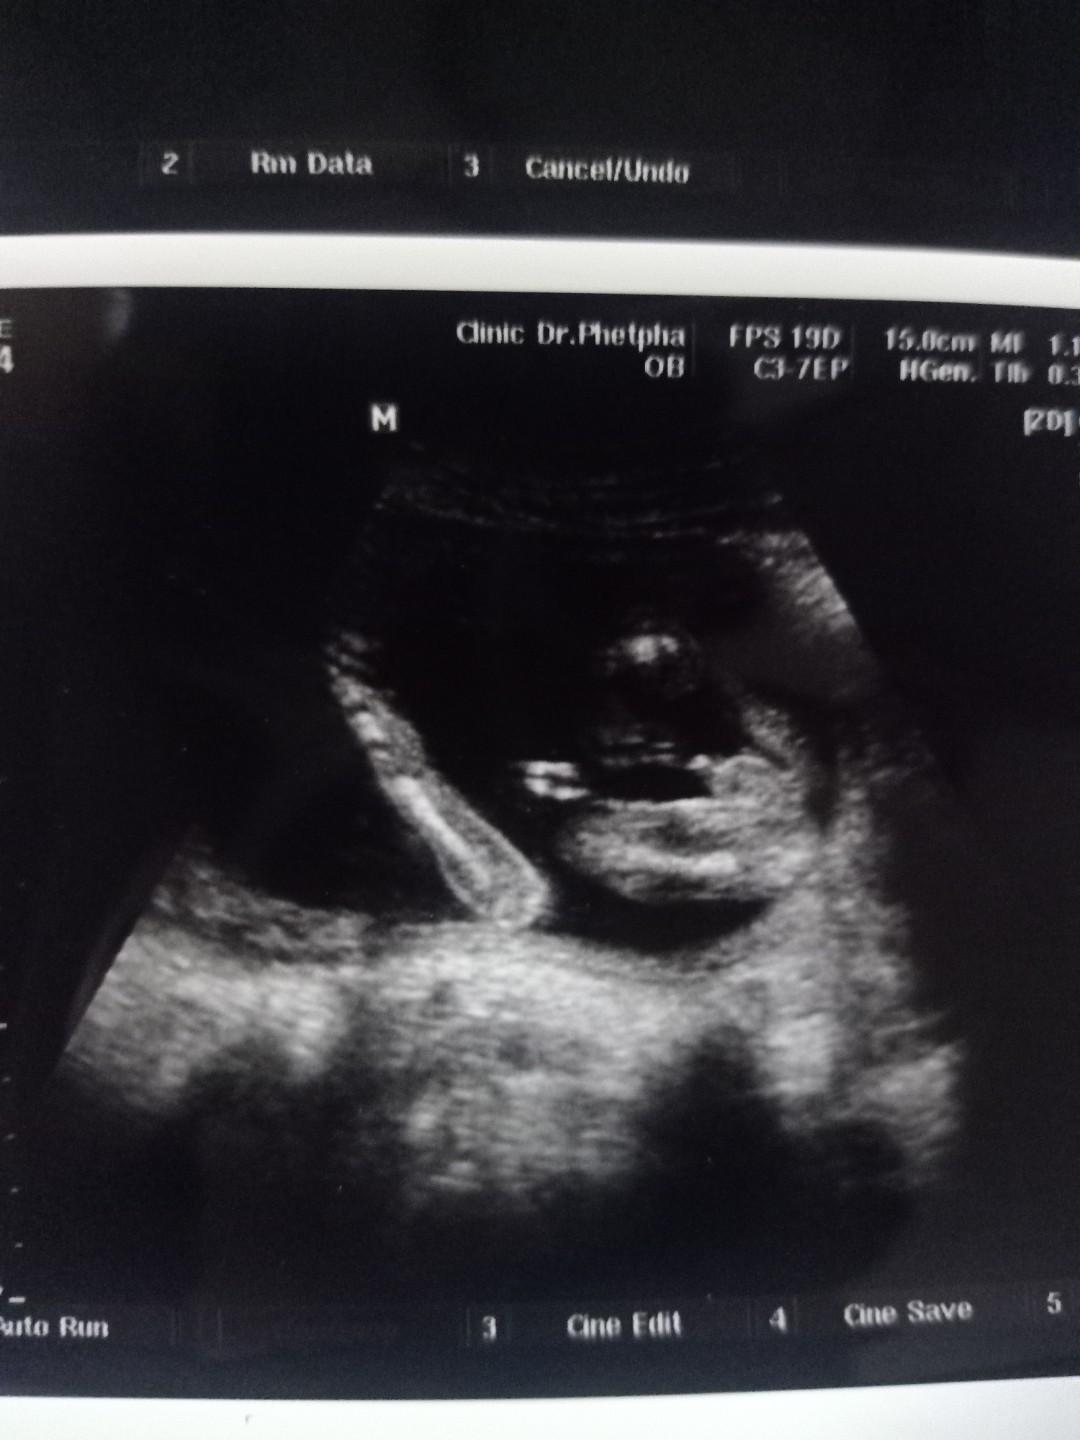

ชายคะ👶

ผช.ค่าา

ชาย จรา